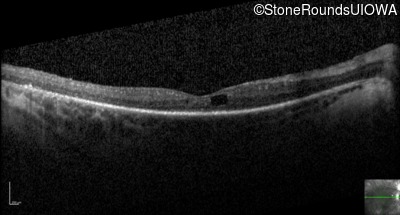

Optical Coherence Tomography - Left - 20/70 +1

Exemplar / OCT Stack